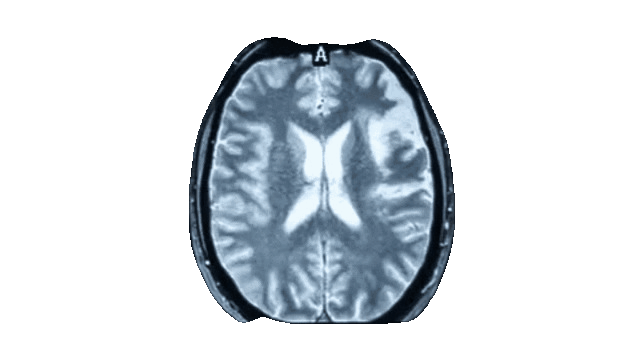

בימים אלו מוקם מאגר המוחות הגדול בישראל באוניברסיטת תל אביב - המאגר עתיד להכיל 25,000 מתנדבים בריאים וישלב מידע מוחי, פיזיולוגי ואישיותי

מאגר המוחות של אוניברסיטת תל אביב כולל מידע מפורט של פעילות ומבנה המוח, לצד מידע פיזיולוגי ואישיותי. איחוד של כל המידע יאפשר התבוננות רחבה יותר ואיפיון מדויק של האוכלוסיה המקומית על כל נגזרותיה, מבחינה חברתית, כלכלית, פוליטית, מגזרית ועוד.

3. סריקת MRI של המוח - סריקה לא פולשנית בת שעה הכוללת רצפים מבניים ותפקודיים